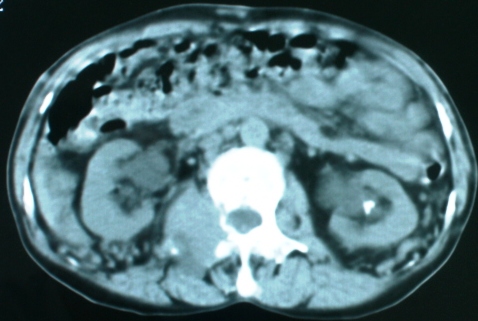

以下是引用zsl6918在2008-11-4 19:14:00的发言:[br]多发转移性改变,子宫改变不除外为原发灶